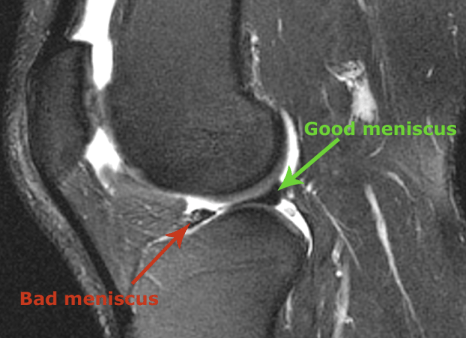

Below is a side view of my knee, from the MRI. The dark area where the green arrow is pointing, is what the entire meniscus is supposed to look like. The damaged area of the meniscus is pointed out with the red arrow.